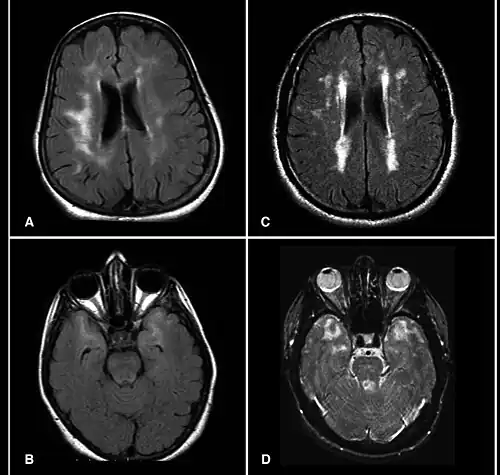

CADASIL is an inherited disorder caused by mutations in the NOTCH3 gene located on chromosome 19.[19] NOTCH3 codes for a transmembrane protein whose function is not well-known. However, the mutation causes accumulation of this protein within small to medium-sized blood vessels.[19] This disease often presents in early adulthood with migraines, stroke, mood disturbances, and cognitive deterioration. MRI shows white matter changes in the brain and also signs of repeated strokes. The diagnosis can be confirmed by gene testing.[20]

MRI demonstrating white matter changes in the brain of patients with CADASIL -

Brain infarct